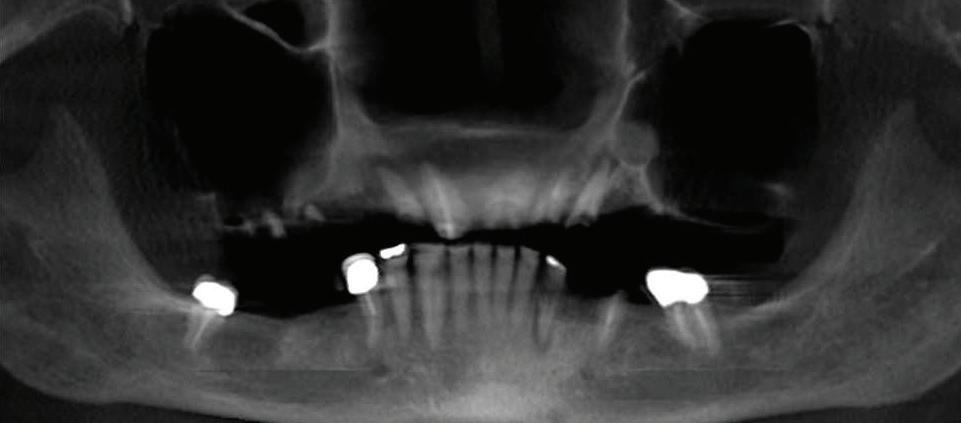

Submitted By Sivakumar Sreenivasan, DMD, MDS

Dental Implant Center of Rockville

Can just four implants replace all of the teeth on the top or the bottom of your mouth? Thanks to advances in dental implant technology, that answer is a resounding yes.

Here’s where it gets really interesting: You do not need a dental implant for each and every one of your missing teeth. All you need is four precisely placed implants on the top of your mouth, and four on the bottom, to restore your full smile. That’s the beauty of the all-on-four. And because the implant is made of titanium, it has the unique ability to fuse to living bone and function as part of it. So eventually, the dental implant becomes part of the jawbone and serves as a strong, long-lasting foundation for your new teeth.

Next, they will begin the implantation process. This means they will

insert the titanium screws into your jawbone. Most likely, they will place two implants toward the front of your mouth and two towards the back of your mouth so the “anchors” can evenly bare the force of the denture.

How Do You Know If The All-On-Four Procedure Is The Right Option For You?

At your All-On-Four consultation, you’ll receive a 3D CT Scan. This scan will help determine if you need implants and assist your doctors in creating your treatment plan. So if you want to learn more about dental implants, simply schedule a consultation with an All-On-Four provider. It’s the best way to find out how dental implants can change your life.